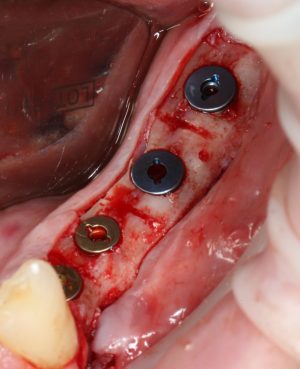

Кстати, обрати внимание на ширину альвеолярного гребня (левая картинка). Она чуть меньше 3 мм. Это объясняет, почему я засомневался в возможности установки имплантатов одновременно с остеопластикой. Понятно и без КЛКТ.

Возвращаемся к основной операционной области. Еще раз посмотрим на альвеолярный гребень, поофигеваем от его ширины и моих грандиозных планов:

Я зафиксировал костный блок практически без адаптации на несколько винтов. Обрати внимание, что винты находятся в зоне, где не планируется установка имплантатов. Фиксация должна быть надежной, поскольку мне еще предстояла подготовка лунок для имплантатов. Трех винтов для этого вполне достаточно.

Глянем на то, что получилось: